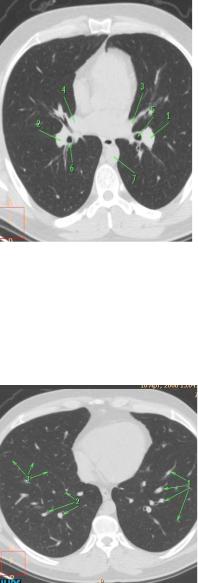

Рис. 23. КТ на уровне верхних

долей в легочном электронном окне: 1 – контур верхнего средостения; 2 – трахея;

3, 4 – легочный рисунок – различные сечения мелких веточек сосудов

Легкие отображаются темно-серыми полями, на фоне которых видны продольные и поперечные сечения кровеносных сосудов, а также просветы бронхов, форма которых зависит от соотношения плоскости сканировании и плоскости расположения бронха.

На высокоразрешающих компьютерных томограммах просветы бронхов можно проследить до V-го порядка. Основные анатомические элементы грудной полости обозначены на рисунках 23-30, где представлены компьютерные томограммы на верхнем, среднем и нижнем уровнях в легочном (рис. 23 -27) и средостенном режимах (рис. 2830).